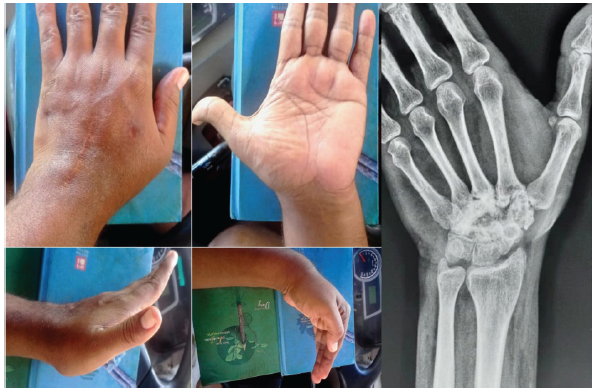

A 38-year-old right-hand–dominant male from Northern Kerala presented to us with progressive pain and swelling of his left wrist for a duration of 4 years. He had initially undergone evaluation for the same complaints 4 years ago, when the swelling was smaller, and X-ray and magnetic resonance imaging (MRI) at that stage were suggestive of a simple bone cyst or enchondroma, and the condition was managed non-operatively. One year before presentation, his symptoms increased and a fresh MRI was suggestive of GCT of the carpal bones. At this stage, he underwent intralesional curettage with cancellous bone grafting at an outside center and biopsy confirmed it to be GCT of the carpal bones. 8 months later, he presented to us with recurrent pain, swelling, and decreased wrist motion (Fig. 1).

Figure 1: Clinical images (top left) depicting the pre-operative range of motion at the left wrist; pre-operative antero-posterior radiograph showing relative lucencies in the carpals and proximal ends of the metacarpals and reduced inter-carpal clear spaces (top right); sagittal, coronal, and axial T1 and T2/short tau inversion recovery magnetic resonance imaging sequences of the left wrist showing a lobulated expansile lesion (bottom row).

The patient’s family history was negative for similar conditions. He claimed to be a non-smoker and non-alcoholic. He did not have any comorbidities. On examination, the patient had a firm, tender, non-mobile swelling of size 7 × 6 cm over the dorsum of the wrist extending to the hand. Visual analogue score (VAS) was 6/10. Ranges of motion (affected/healthy side) were 40◦/80◦ of dorsiflexion, 40°/80° of palmar flexion, 90/90° of pronation, and 90/90° of supination. No limitations to the range of motion (ROM) were seen for any of the fingers.

Plain radiographs revealed lucencies in the distal carpal row and bases of 2–4 metacarpals with reduction in the clear spaces between individual bones (Fig. 1). Contrast-enhanced MRI demonstrated a relatively well-defined lobulated expansile lesion involving the distal row of the carpal bones with contiguous spread to the bases of the 2nd and 3rd metacarpals, measuring ~51 × 37 × 41 mm (Fig. 1). The mass abutted the volar flexor tendons at the capitate level and extended dorsally between the 3rd and 4th extensor compartments into subcutaneous tissue. It was bounded laterally by the abductor pollicis longus and medially by the extensor carpi ulnaris. There was mild erosive change at the 4th metacarpal base and scaphoid with marrow edema in the lunate and triquetrum. Signal characteristics were t1-intermediate and T2/short tau inversion recovery hyperintense with internal septations showing Gradient Recalled Echo blooming; enhancement was heterogeneous with non-enhancing areas – overall features suggestive of a locally aggressive GCT recurrence. Routine blood investigations and infection panel were negative. Serum Parathyroid hormone was within normal limits, ruling out Brown tumor. The chest radiograph was clear.